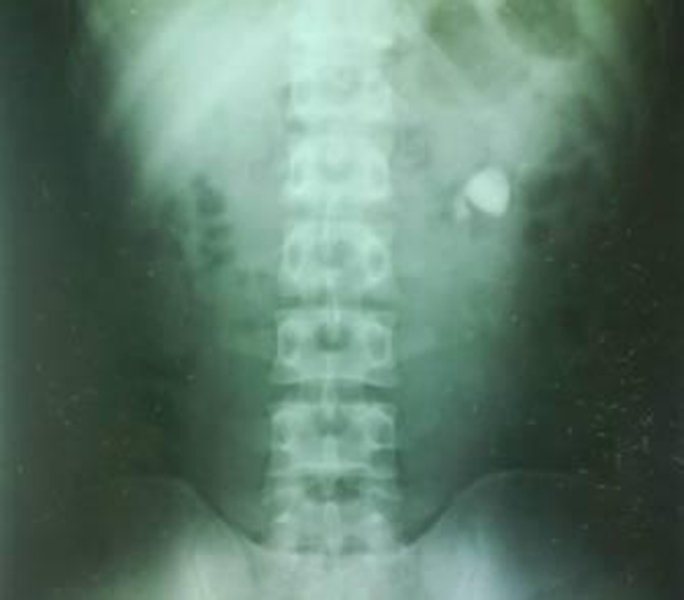

雙腎結石的